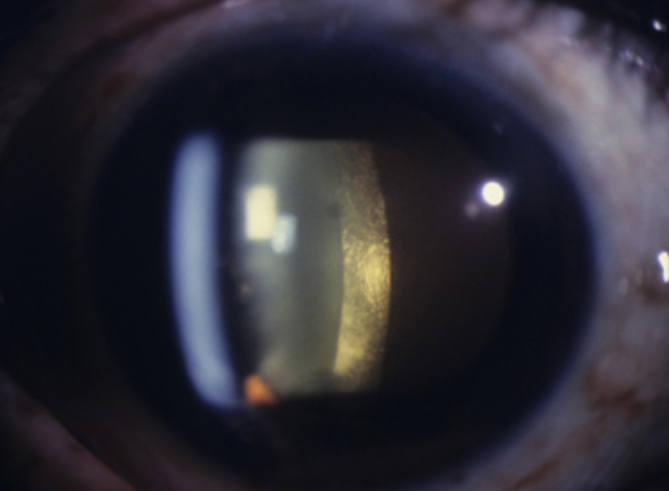

– une acuité visuelle à 5/10 aux deux yeux avec une correction de +1,00 -1 à 90° à droite et +1,75 -1,25 à 85° à gauche ;